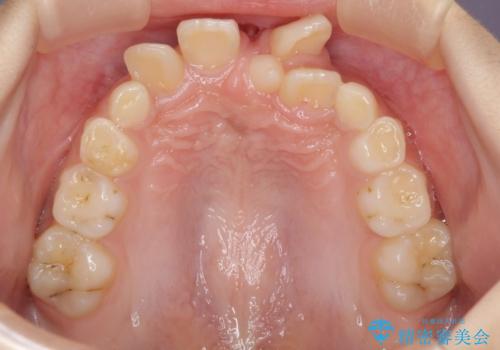

- 前歯の叢生を気にして来院された、小学校3年生女児の患者様です。

身長がやや低く、乳歯から永久歯への交換が少し遅い印象があったので、ワイヤー装置による1期矯正治療ではなく、乳歯も積極的に動かすことのできるインビザライン・ファーストにて治療を行うこととしました。

上顎前歯に過剰歯があったため、まずはその歯を抜歯し、傷が治癒したタイミングでインビザラインを発注することとしました。

インビザライン・ファーストは1.5年から2年程度の治療期間という制約がありますが、成人矯正(2期治療)をスムーズに行うための下準備期間として位置づけられており、2期治療を比較的安価かつ短期間で行うことができるようになります。